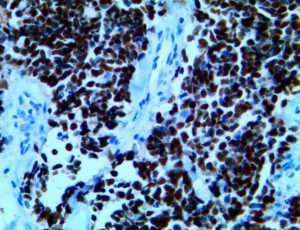

It is the ICU physician who is most likely to witness one of the deadliest manifestations of the abnormal immunological response, the cytokine storm syndrome (CSS). This response is also referred to by some as the cytokine release syndrome (CRS). CSS is characterized by continuous activation and expansion of macrophage and lymphocyte populations, which secrete large amounts of cytokines, causing the cytokine storm. This massive cytokine release is akin to hemophagocytic lymphohistiocytosis (HLH) disease, a syndrome characterized by initial unchecked and persistent activation of cytotoxic T lymphocytes and NK cells.

Clinical and laboratory manifestations of HLH include fever, enlarged liver and/or spleen, neurologic dysfunction, coagulopathy, liver dysfunction, cytopenias (i.e., low levels of erythrocytes, leukocytes, and/or platelets), hypertriglyceridemia, hyperferritinemia, hemophagocytosis, and eventually diminished NK cell activity as the immune system becomes progressively paralyzed. HLH can be familial (primary HLH) or secondary to another disease process (sHLH), such as rheumatic disease, in which it is referred to as macrophage activation syndrome (MAS, characterized by elevated ferritin).